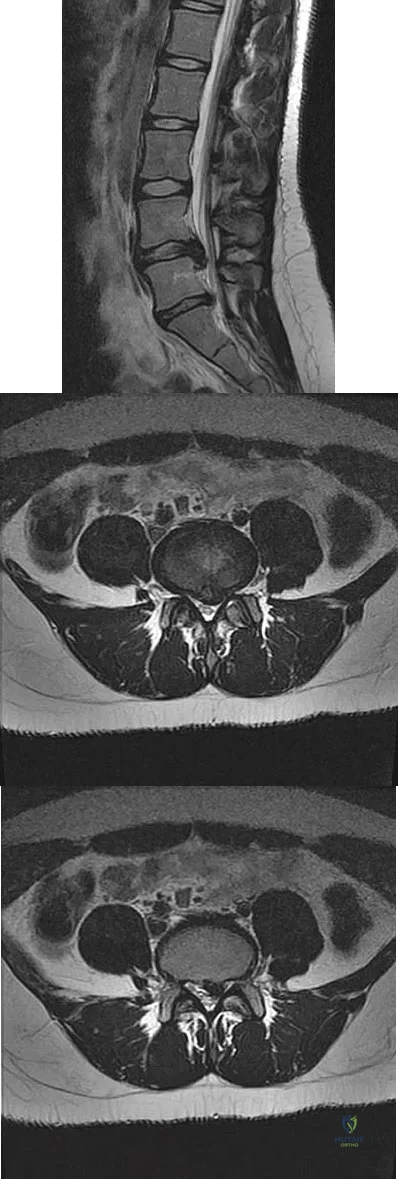

An otherwise healthy 54-year-old man who underwent a successful multilevel lumbar decompression and fusion 4 years ago now reports increasingly severe bilateral thigh claudication with paresthesia and severe back pain for the past 12 months. Physical therapy, bracing, and epidural steroids have failed to provide relief. A radiograph and MRI scans are shown in Figures 15a through 15c. He is afebrile, and laboratory studies show an erythrocyte sedimentation rate of 5 mm/h and a normal WBC count. What is the best course of action?

Explanation